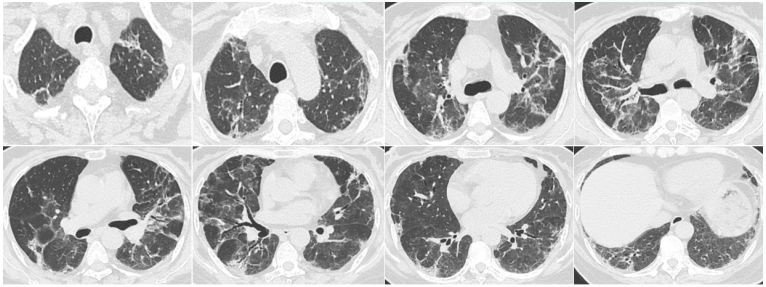

727随访胸部CT:双肺炎症渗出较前吸收良好,遗留间质样改变(图6)。考虑可能是前期病毒感染所致。

图片

6  复查胸部CT(2024-07-27)